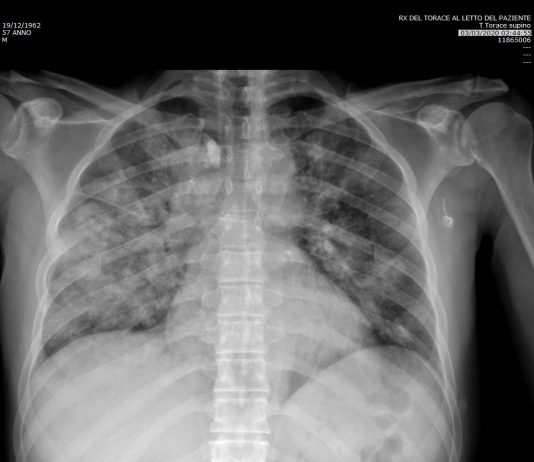

Uomo 57 anni, nessuna comorbidità nota.

Febbre e tosse non produttiva.

Leucocitosi. Insufficienza respiratoria ipossemica e ipocapnica.

Sospetto contatto con soggetti zona rossa. Tampone positivo NCOV 19.

HRTC Torace